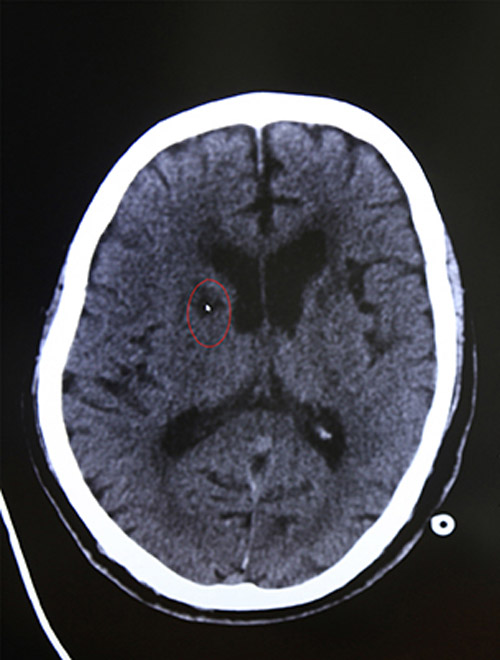

急診CT示:排除腦出血

16:44 影像科3分鐘出報(bào)告,CT報(bào)告顯示:排除腦出血。為進(jìn)一步查看腦血管情況,又迅速完成了顱腦血管磁共振檢查,結(jié)果顯示:腦梗塞。